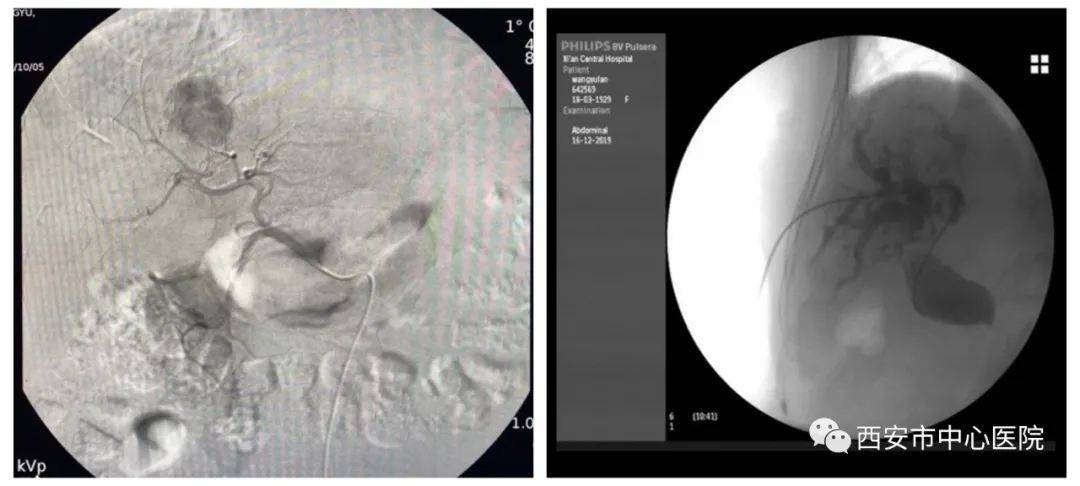

TACE术→PTCD术